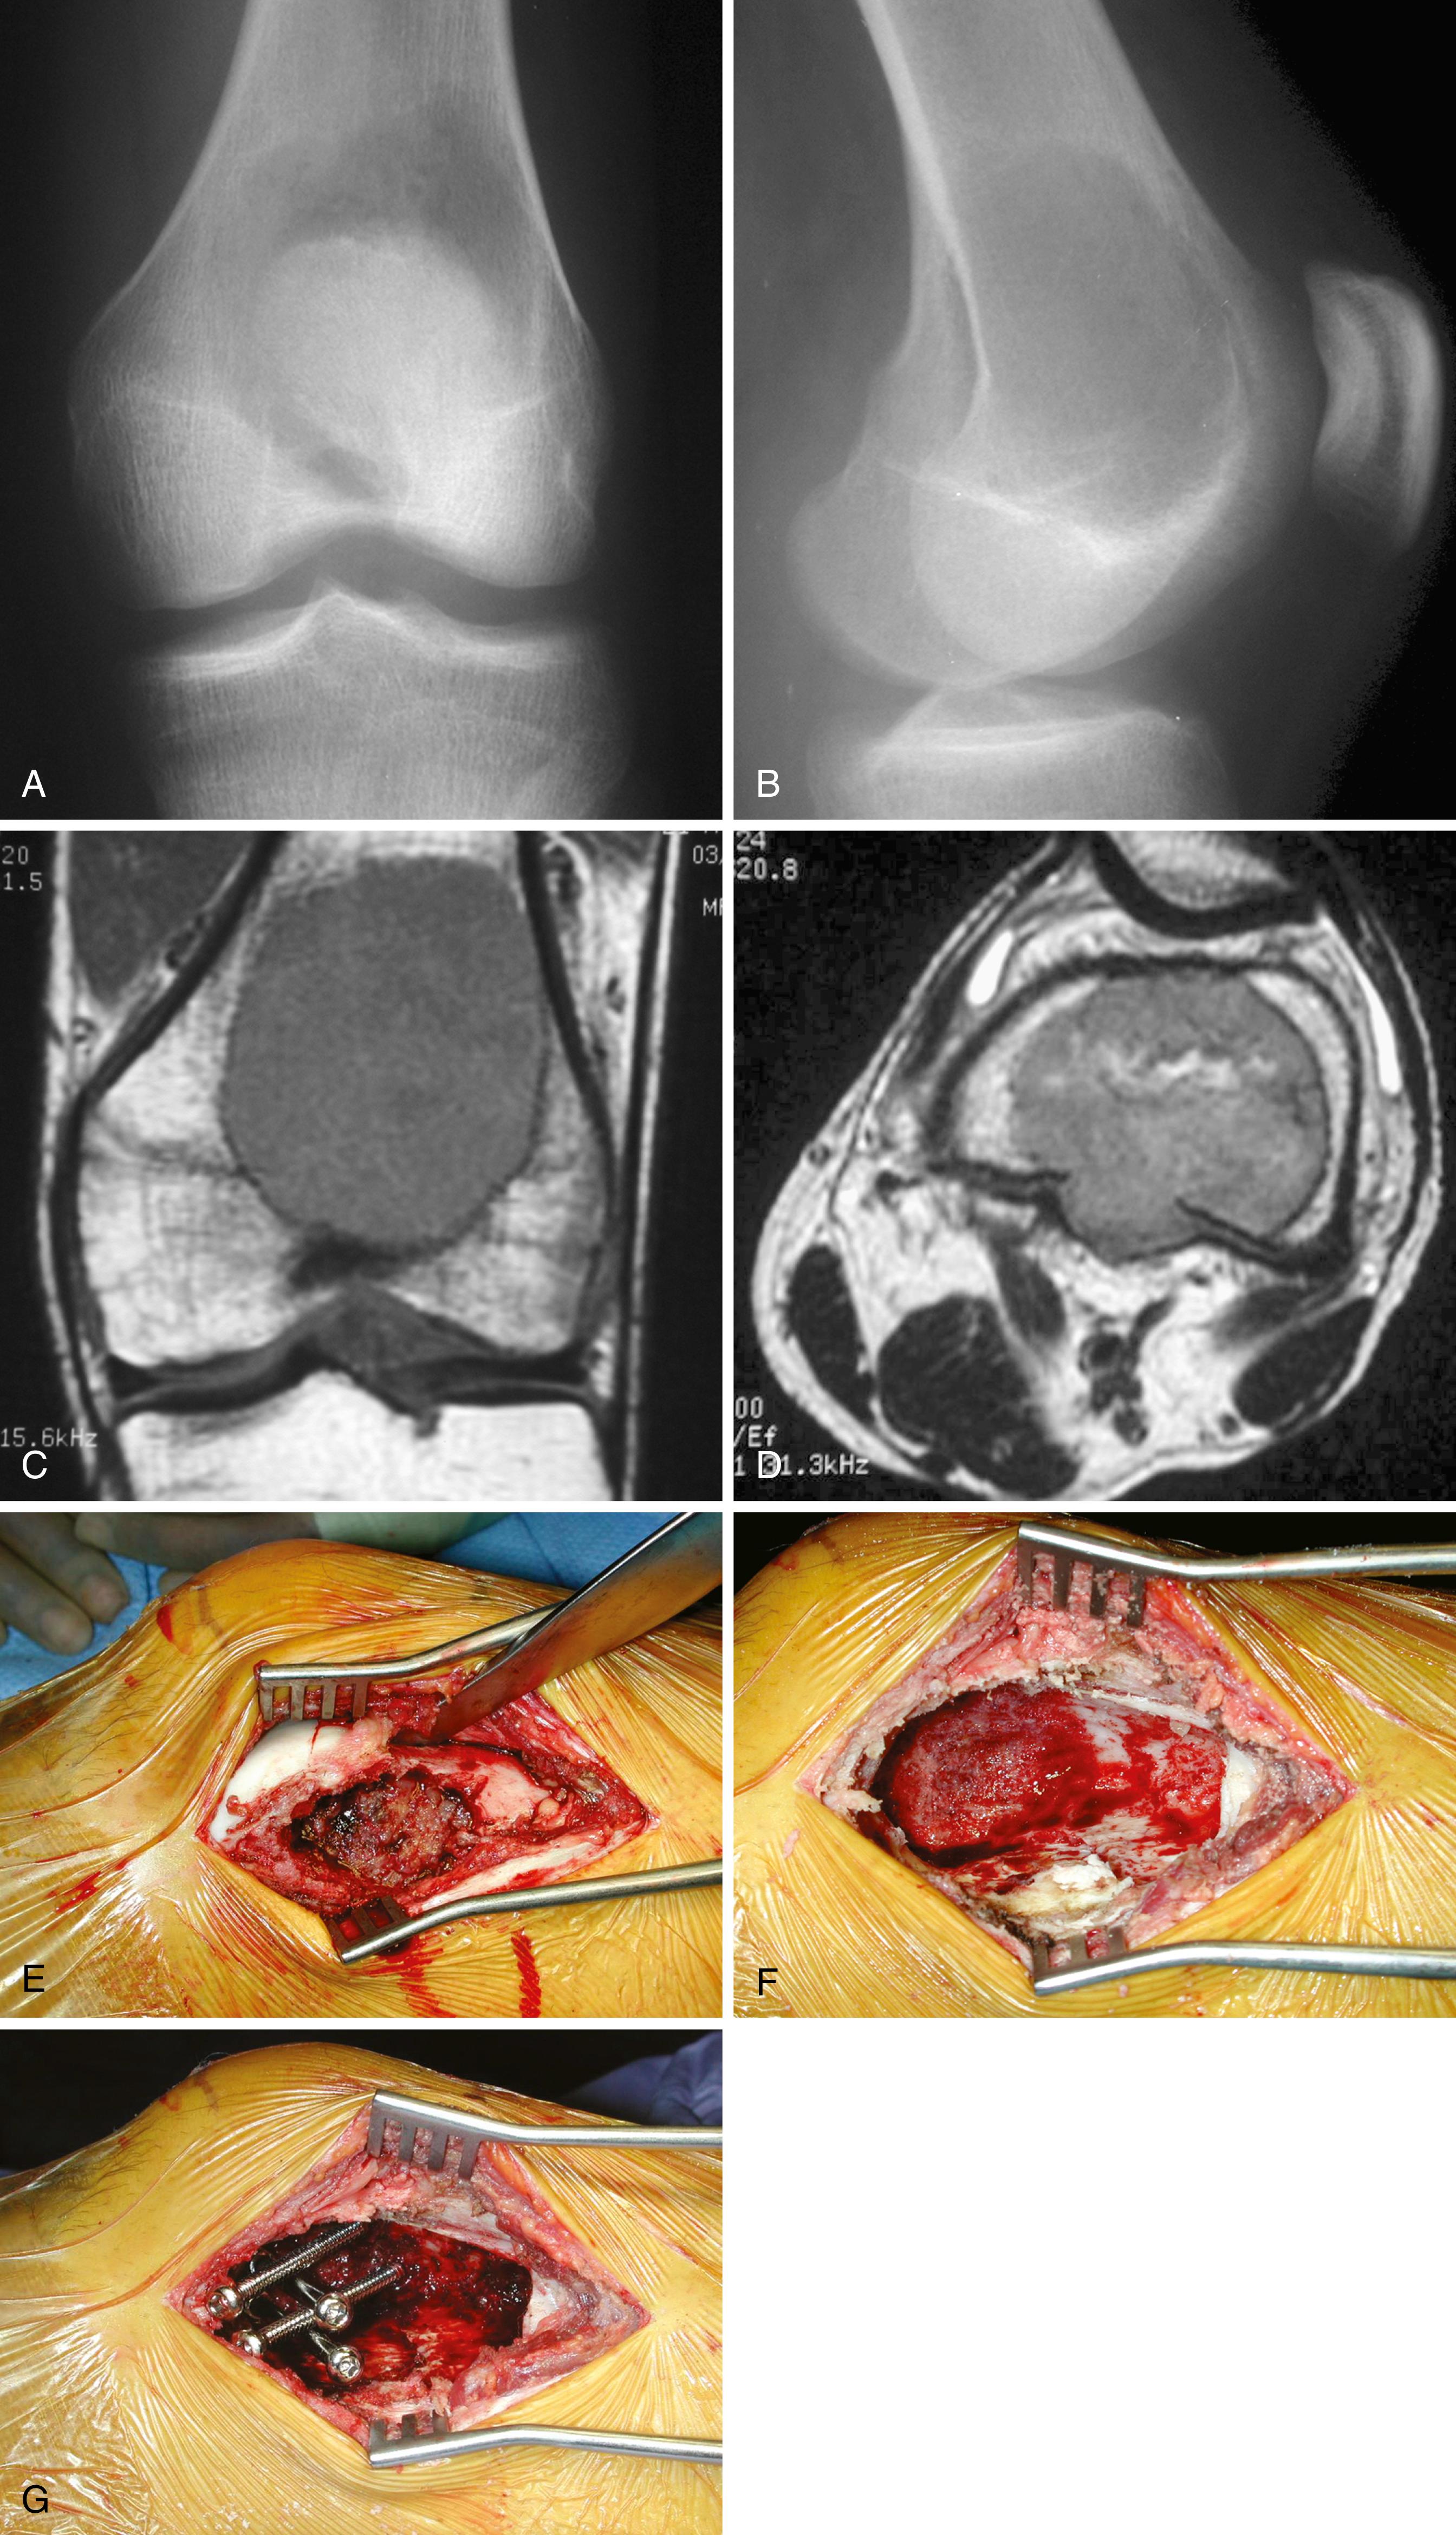

FIGURE 26.2, A and B, Anteroposterior and lateral radiographs of the proximal tibia of a 41-year-old woman with a giant cell tumor. The lesion is radiolucent without a sclerotic rim, is eccentric, and abuts subchondral bone. C and D, Anteroposterior and lateral radiographs of the proximal tibia after curettage and placement of cement and divergent screws.

En bloc wide resection may be required in some stage 3 tumors, cases of local recurrence, and tumors recalcitrant to other methods of intervention. Around the knee, a hemicondylar osteoarticular allograft reconstruction or a rotating hinge endoprosthesis may be necessary ( Fig. 26.3 ). For aggressive lesions of the distal radius, primary resection and reconstruction with a proximal fibular autograft (either as an arthroplasty or as an arthrodesis) may be indicated ( Fig. 26.4 ). For lesions in expendable bones (e.g., the distal ulna, clavicle, or proximal fibula), primary resection without reconstruction may be indicated. For inoperable lesions in the spine or pelvis, irradiation or embolization (or both) may be used ( Fig. 26.5 ); however, caution is advised because of the risk of sarcomatous change in patients treated with irradiation. In patients with pulmonary metastases, resection should be attempted. Chemotherapy has limited success, and irradiation should be reserved for symptomatic inoperable lesions.

FIGURE 26.3, Anteroposterior (A) and lateral (B) radiographs of a 28-year-old man with a giant cell tumor of the right distal femur. Axial (C) and coronal (D) CT reconstructions demonstrate extensive bone destruction and an intraarticular pathologic fracture. The decision was made to proceed with en bloc resection and endoprosthetic reconstruction. Anteroposterior (E) and lateral (F) postoperative radiographs. Patient currently is doing well 8 years after surgery.